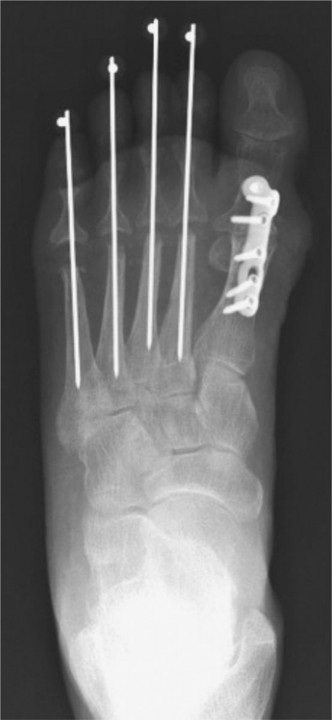

Clinical & Radiographic Imaging